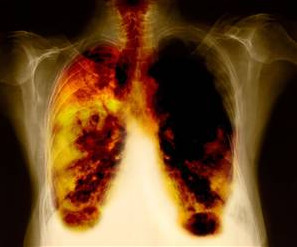

呼吸系统:24小时的污染受害者

雾霾,这是未来30至50年困扰我国民众健康的首要问题。研究表明,80个PM2.5颗粒就能堵死一个肺泡,以目前中国的雾霾天估算,只需三年就能堵死1亿个肺泡,相当于整个肺的三分之一。专家预测,未来20年,将是我国肺癌的井喷期,预计将有数千万人死于呼吸道疾病。

“呼吸污染”蚕食生命

空气中的各种有害物质,包括细菌、病毒、PM2.5颗粒、粉尘、过敏物、有害气体等等,会通过每时每刻的呼吸,进入呼吸系统,并通过肺泡里的毛细血管进入血液循环,抵达每个器官内部,从而导致各种器官性疾病,免疫系统病变和细胞突变等。目前,由呼吸污染所导致的疾病可达数百种,而且不少都是西医无法治愈的“绝症”。